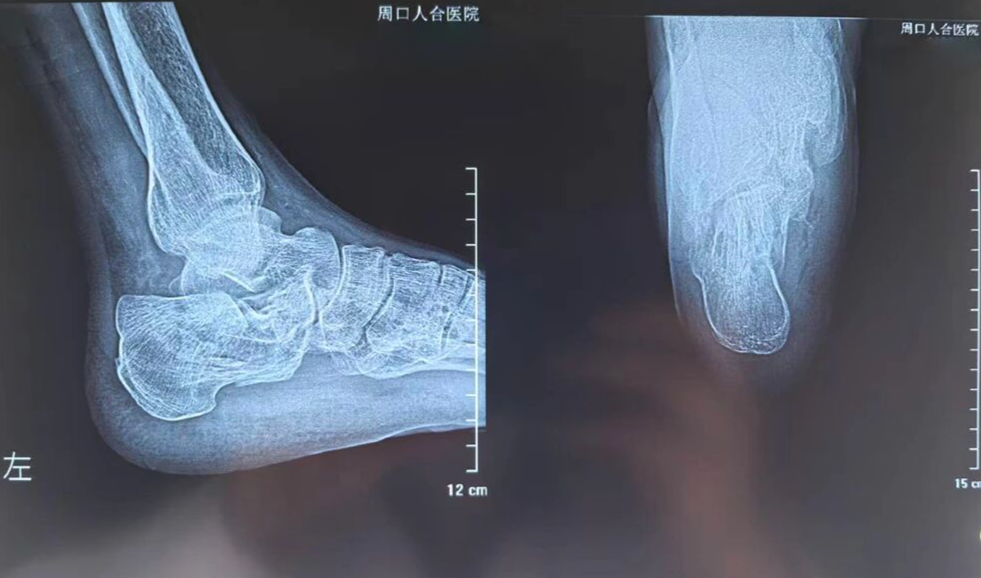

术前

日前,一名高处坠落伤致左侧跟骨粉碎性骨折的患者入院。骨三科团队经充分术前讨论,为其量身定制微创手术方案。术中在X光精准引导下,经皮撬拨复位骨折块,以空心螺钉稳固固定,出血极少、创伤小。术后患者恢复良好,早期即可开展功能锻炼,避免了传统大切口带来的并发症隐患。